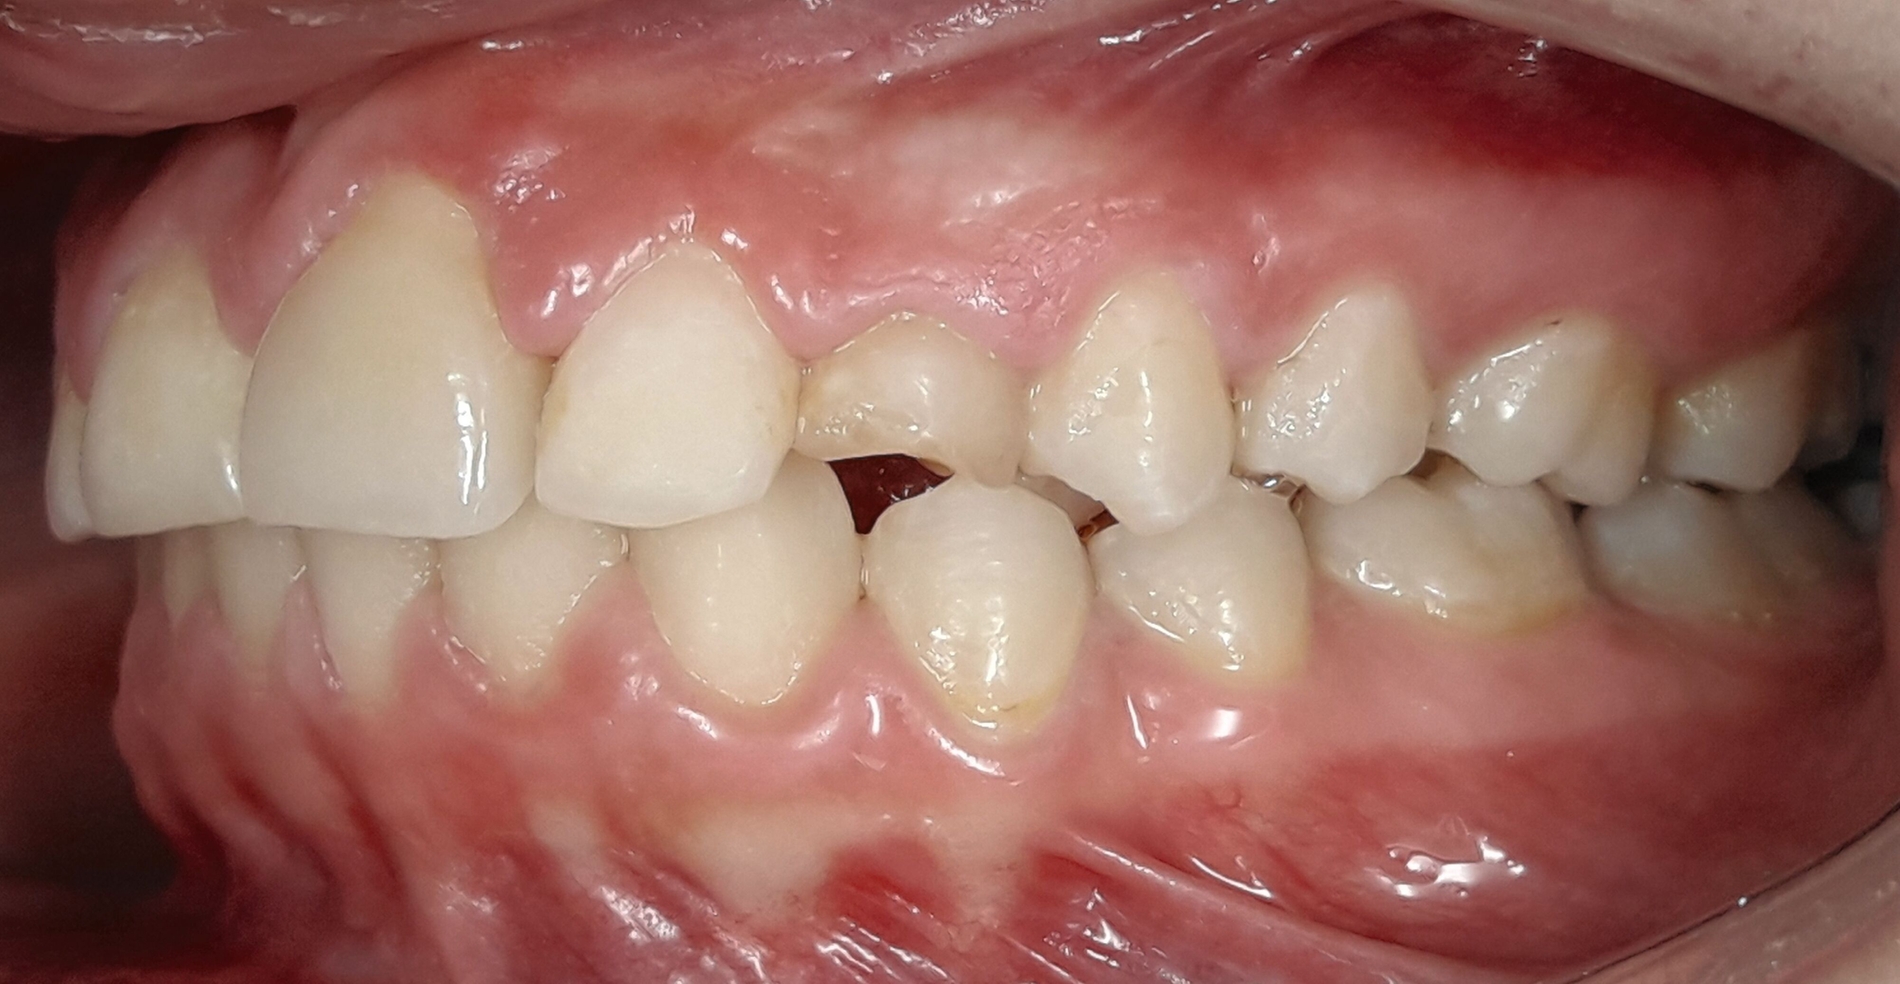

Im Februar 2019 wurde die kieferorthopädische Klinik von der Erstautorin übernommen. Bei der Auswertung der vorgefundenen Daten der Patientin wurde festgestellt, dass der linke obere zentrale Schneidezahn vor sechs Monaten extrahiert worden war. Die festsitzende Apparatur war im Oberkiefer bereits eingegliedert. Die Druckfeder zwischen Zahn 11 und 22 diente zur Lückenöffnung für den späteren prothetischen Ersatz des Zahnes 21. Auch auf den persistierenden linken Milcheckzahn war ein Bracket geklebt. Die Okklusion im Bereich der ersten Molaren war rechts und links neutral (Abbildung 2).